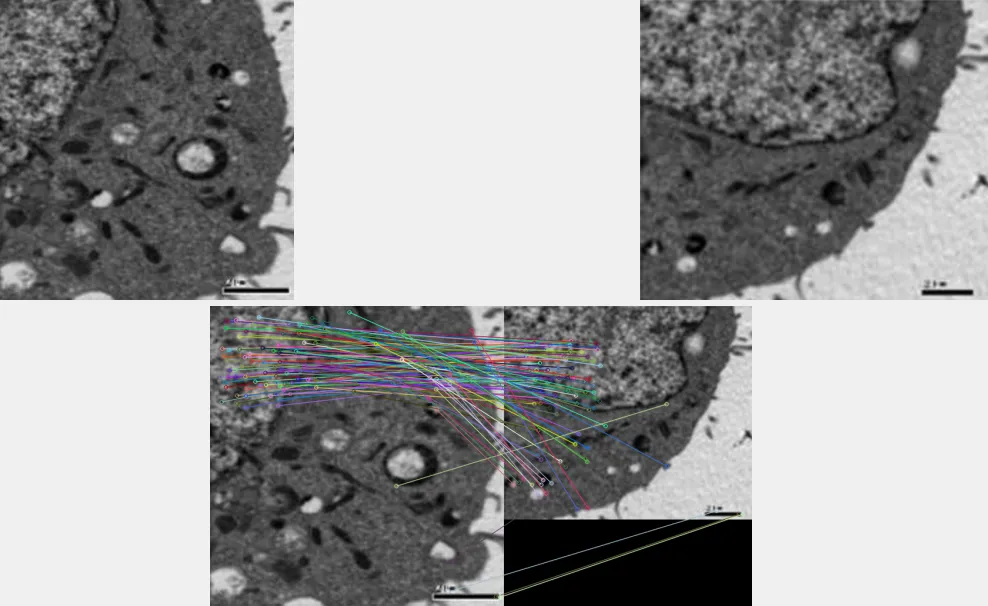

发表在 Journal of Cellular and Molecular Medicine

的一篇标题为 Novel mechanism of miRNA‐365‐regulated trophoblast apoptosis in recurrent miscarriage 的研究论文被 PubPeer 用户质疑存在图像问题。

Henosepilachna firma

在 PubPeer 发表评论:

比预期的更为相似。